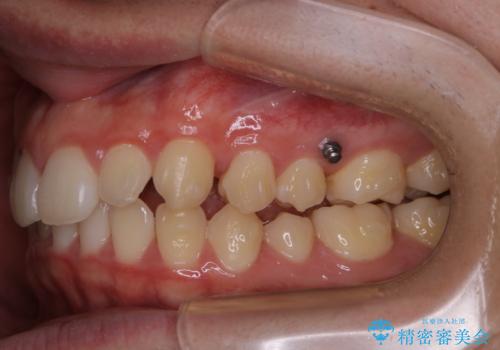

- 上の前歯が見えすぎて気になるとご相談にいらした方です。インビザラインにて前歯の圧下を行うことで歯の見え方の改善し、同時に奥歯の噛み合わせも改善を行いました。

インビザラインを正しく使用して頂けたおかげで、比較的難しいとされる歯の圧下も補助装置を使用せずに行うことが出来ました。上の前歯のラインが整ったことで笑った時の口元の印象を改善させることができ、大変喜んでいただけました。